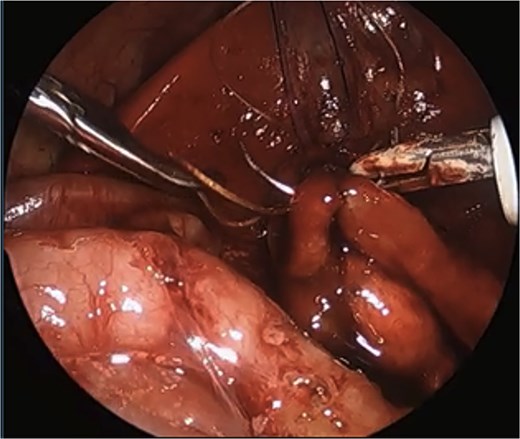

Intraoperatively, the stomach and proximal duodenum were dilated. The gallbladder was large, distended, and densely adherent to the transverse colon. The cecum was in the right middle abdomen with the appendix flipped up toward the gallbladder, attached to the right upper quadrant through adhesions. After taking down the adhesions with hook cautery and dissecting the structures obscuring the field of view for the anastomosis, the pancreas and distal duodenum were visualized. The duodenum was kocherized and the distal duodenum mobilized. A 1.2 cm transverse enterotomy was made in the duodenum, ⁓1 cm proximal to the obstruction, and a similar size longitudinal enterotomy was made distally. A 4–0 PDS percutaneous suture was placed as the first stitch and transfixed over a gauze bolster to elevate the anastomosis and line it up. A duodenoduodenostomy was created by running the posterior anastomotic wall with 4–0 Vicryl cut to 12 cm and ended by tying to itself, and the same was done with another 4–0 Vicryl to run the front wall. The needle tip was bent by the port halfway through the anterior wall as the interior working space was very limited in this tiny premature infant, so that suture was tied to itself, and the rest of the anterior wall was finished with interrupted sutures.

We describe a modification of the port placements during a laparoscopic duodenal atresia repair in a very low birthweight, preterm infant; however, these modifications can be used to optimize repair in any duodenal atresia patient. The modified positioning of the instruments allowed for a working space better triangulated for suturing with both hands at right angles to each other and allowed for the camera to be further away from the target tissue. These modified placements also enabled a more lateral approach, more in line with the rotation of the duodenum, and facilitated easier angles for laparoscopic suturing with a straight-on view of the anastomosis, overall increasing the safety of the procedure and limiting the risk of intraoperative complications (Fig. 4).

Laparoscopic view of anastomosis. The surgery was completed successfully laparoscopically, and the patient had no postoperative complications.